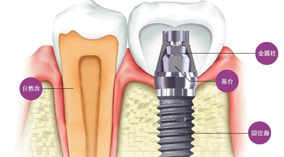

什么是种植牙?

简介:什么是种植牙? 种植牙齿(Dental implant)指的是一种以植入骨组织内的下部结构为基础来支持、固位上部牙修复体的缺牙修复方式。包括下部的支持种植体和上部的牙修复体两... [详情]

01 不伤害邻牙

种植牙完成后,它会依靠自身牙根独立存在,不会影响两侧的健康牙,也是选择种植牙的重要原因之一。

03 稳固牢靠功能长久

种植牙是通过人工牙深度植入在牙槽骨中,与真牙生长构成形态及为类似,能很好地恢复牙齿功能,咀嚼功能大大优于其他传统假牙。